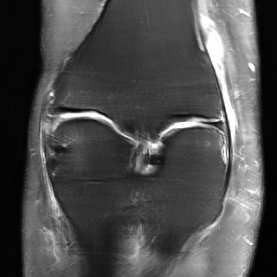

Deep Learning (DL) methods have shown promising results for solving ill-posed inverse problems such as MR image reconstruction from undersampled $k$-space data. However, these approaches currently have no guarantees for reconstruction quality and the reliability of such algorithms is only poorly understood. Adversarial attacks offer a valuable tool to understand possible failure modes and worst case performance of DL-based reconstruction algorithms. In this paper we describe adversarial attacks on multi-coil $k$-space measurements and evaluate them on the recently proposed E2E-VarNet and a simpler UNet-based model. In contrast to prior work, the attacks are targeted to specifically alter diagnostically relevant regions. Using two realistic attack models (adversarial $k$-space noise and adversarial rotations) we are able to show that current state-of-the-art DL-based reconstruction algorithms are indeed sensitive to such perturbations to a degree where relevant diagnostic information may be lost. Surprisingly, in our experiments the UNet and the more sophisticated E2E-VarNet were similarly sensitive to such attacks. Our findings add further to the evidence that caution must be exercised as DL-based methods move closer to clinical practice.

翻译:深度学习(DL)方法在解决错误的反向问题(例如用未充分抽样的美元空间数据进行MR图像重建)方面显示了有希望的结果。然而,这些方法目前没有重建质量的保证,这种算法的可靠性也只是不太为人所知。反向攻击为了解基于DL的重建算法的可能失败模式和最差的成绩提供了宝贵的工具。在本文中,我们描述了对多油美元空间测量的对抗性攻击,并对最近提议的E2E-VarNet和一个更简单的UNet模型进行了评价。与以前的工作不同,这些攻击的目标是具体改变诊断相关的区域。我们使用两种现实的攻击模型(对抗的美元空间噪音和对抗性旋转)能够表明,目前基于DL的重建算法对于这种扰动确实十分敏感,以致可能丢失相关的诊断信息。令人惊讶的是,在我们的实验中,UNet和更为复杂的E2E-VarNet对此类攻击同样敏感。我们的调查结果进一步表明,必须更接近以DL为基础的临床方法。